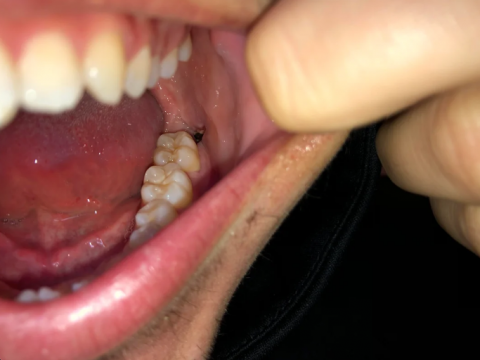

Both Image A and Image B show a dark, well-defined radiolucent area surrounding the root apex of one of the anterior teeth. This appearance is consistent with:

Periapical abscess

Periapical cyst

Chronic apical granuloma

Chronic apical periodontitis